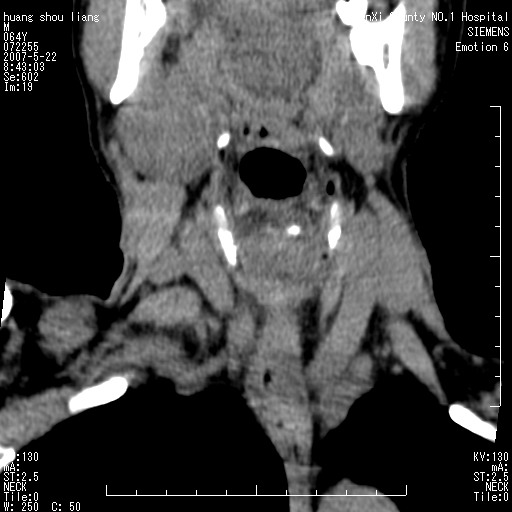

男性,64岁。颈部包块8年。最近增大。

对不起大家,可能是片子发太多有点乱,正常腮腺在下颌角的外侧,颌下腺在下颌体的中部内侧,本例在下颌角内侧偏下,和腺体一点关系都没有,从vrt和mpr上可以很明显看出来,再者肿块是好多粘连在一块的,大家在仔细看看,左侧可能也是吧,我还是考虑为肿大的淋巴结融合在一块,但性质??????

右侧腮腺下部均匀软组织密度肿块,外形不规则,与周围组织分界清晰,考虑右侧腮腺混合瘤或多形性腺瘤。

大家好,病理结果出来了,如大家所说,颌下腺混合瘤。

唉,解剖没学好吧,我诊断错了,不过还是有些不理解回去我在多看看书,谢谢大家的参与,以后我还会奉献好的病例。